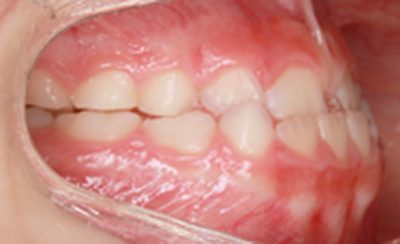

As imagens abaixo demonstram o mesmo caso de mordida cruzada anterior com fotografias intra orais laterais. Observe que os incisivos superiores, que se encontravam inicialmente atrás dos incisivos inferiores, passou a ocluir corretamente.